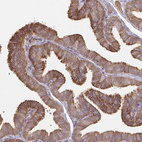

Immunohistochemical staining of human breast shows strong membranous and cytoplsmic positivity in glandular cells.